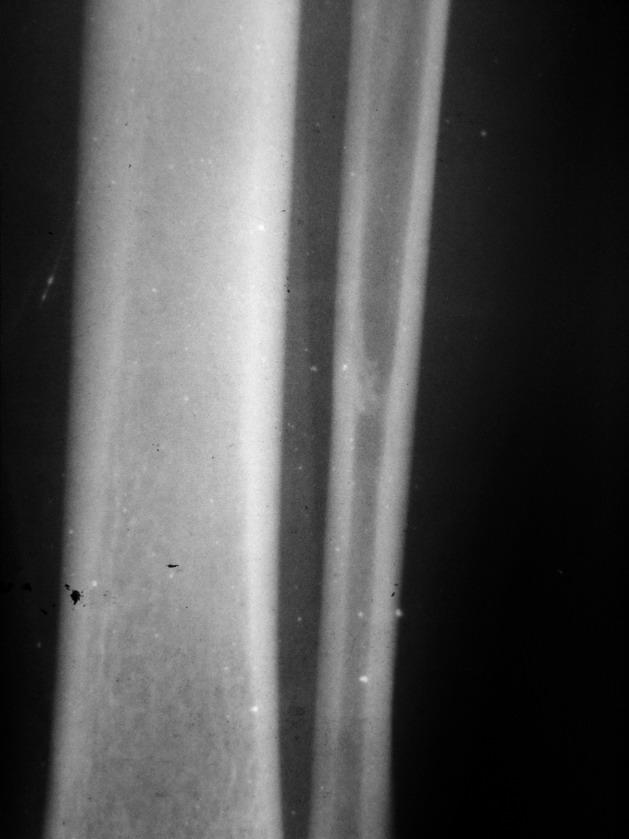

患者 男26岁 左胫腓骨扭伤

1、外踝骨折。

2、腓骨下端内生骨瘤,即骨岛。

支持  左侧外踝骨折,左腓骨中下段骨岛。